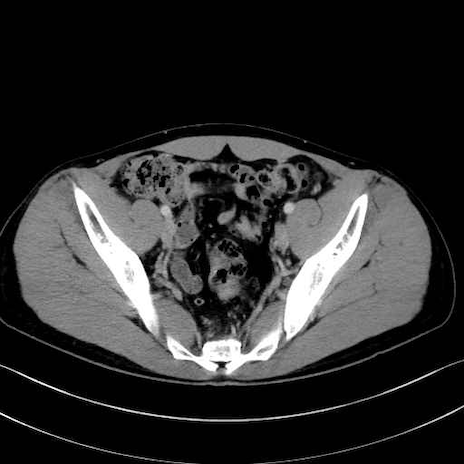

内閉鎖筋 (Obturator internus)